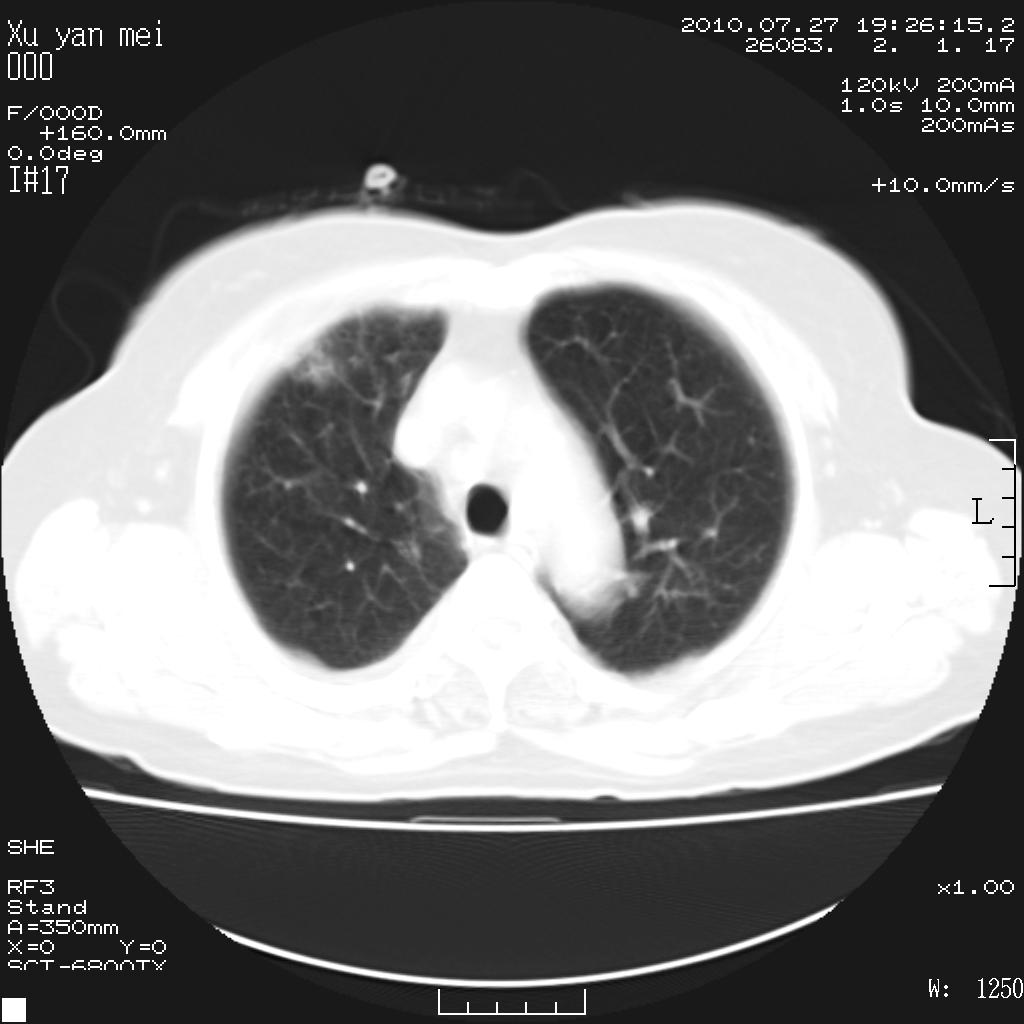

女,60岁,胸痛就诊,右肺结核?炎症?其它?(胸片右侧中上肺野确实看不到什么啊)

1)考虑两肺感染性病变;建议抗炎治疗后复查。2)双侧少量胸腔积液。

1)考虑两肺感染性病变;建议抗炎治疗后复查。2)右侧少量胸腔积液。

双肺炎症可能性大,建议抗炎后复查。右侧胸腔少量积液。双侧胸膜轻度增厚。

考虑两肺感染性病变;不除外肺栓;建议抗炎治疗后复查。